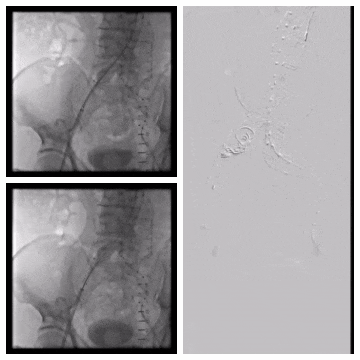

造影示肾下腹主动脉瘤

选用28-14-140mm主动脉覆膜支架

释放短腿(交叉腿)

导丝超选右髂支

右侧延续16-18-140mm髂支

左侧延续16-18-140mm髂支

术中释放右侧髂支后,患者突发腹痛、心率增快、血压下降,造影怀疑右髂动脉破裂,紧急加放髂支并弹簧圈栓塞。